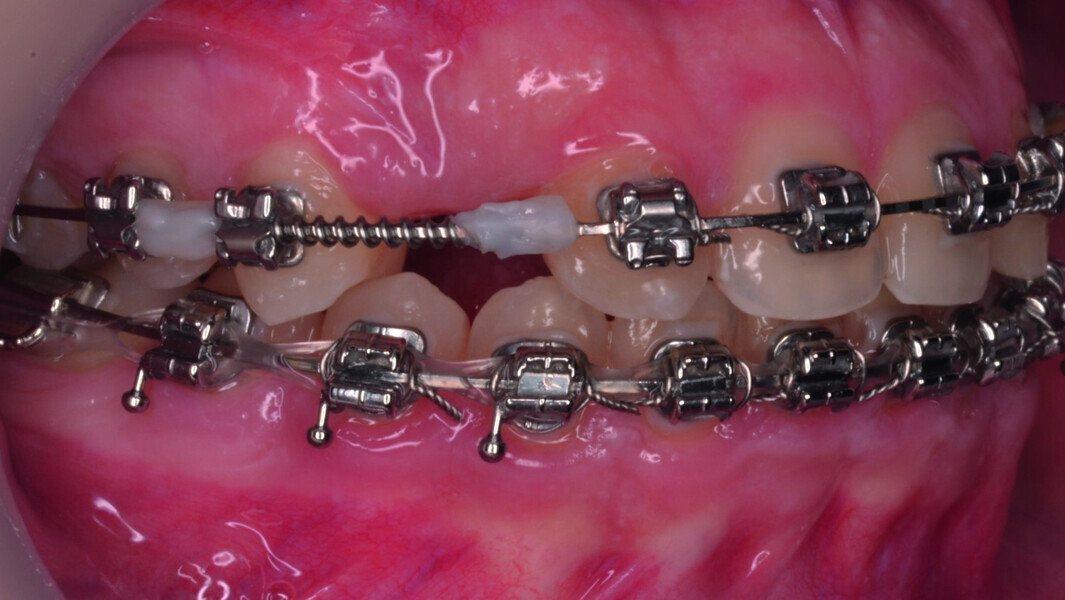

Orthodontic management of maxillary lateral incisors agenesis